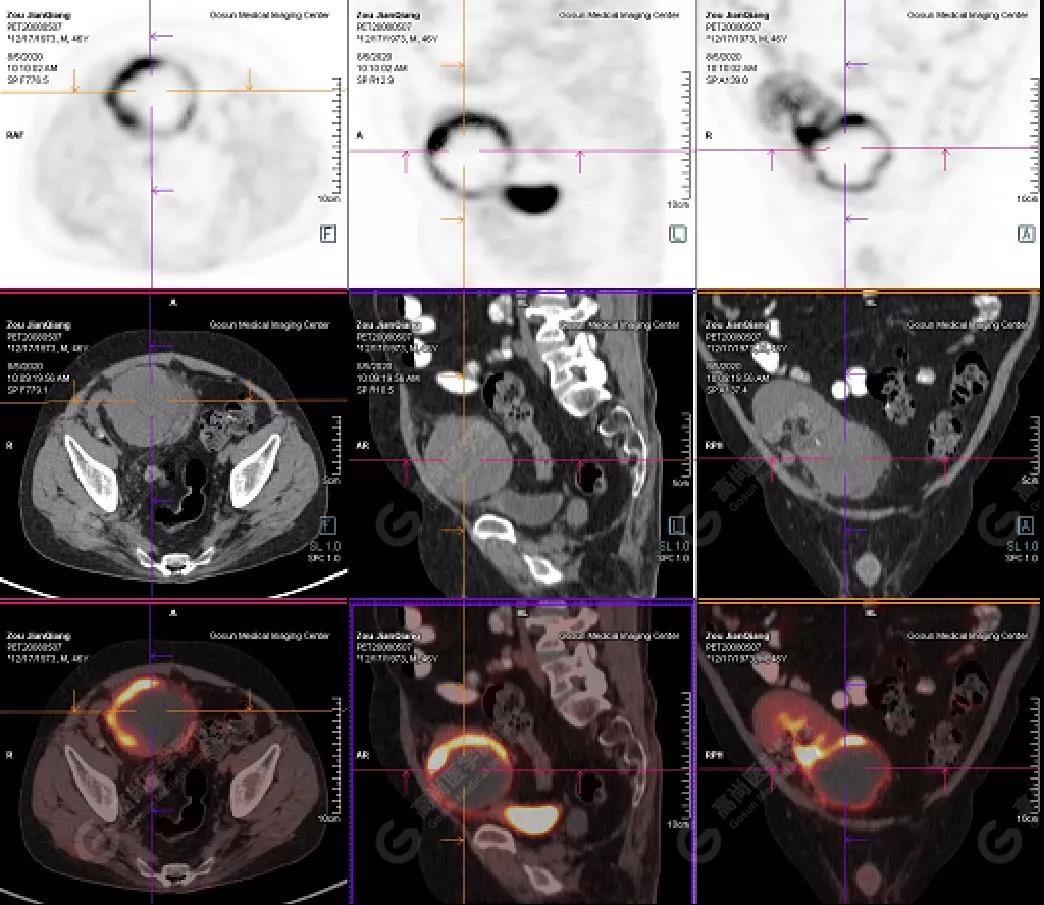

PET/CT檢查

↑移植腎下部等密度腫塊,代謝環(huán)狀增高,SUVmax13.4,中心代謝缺損